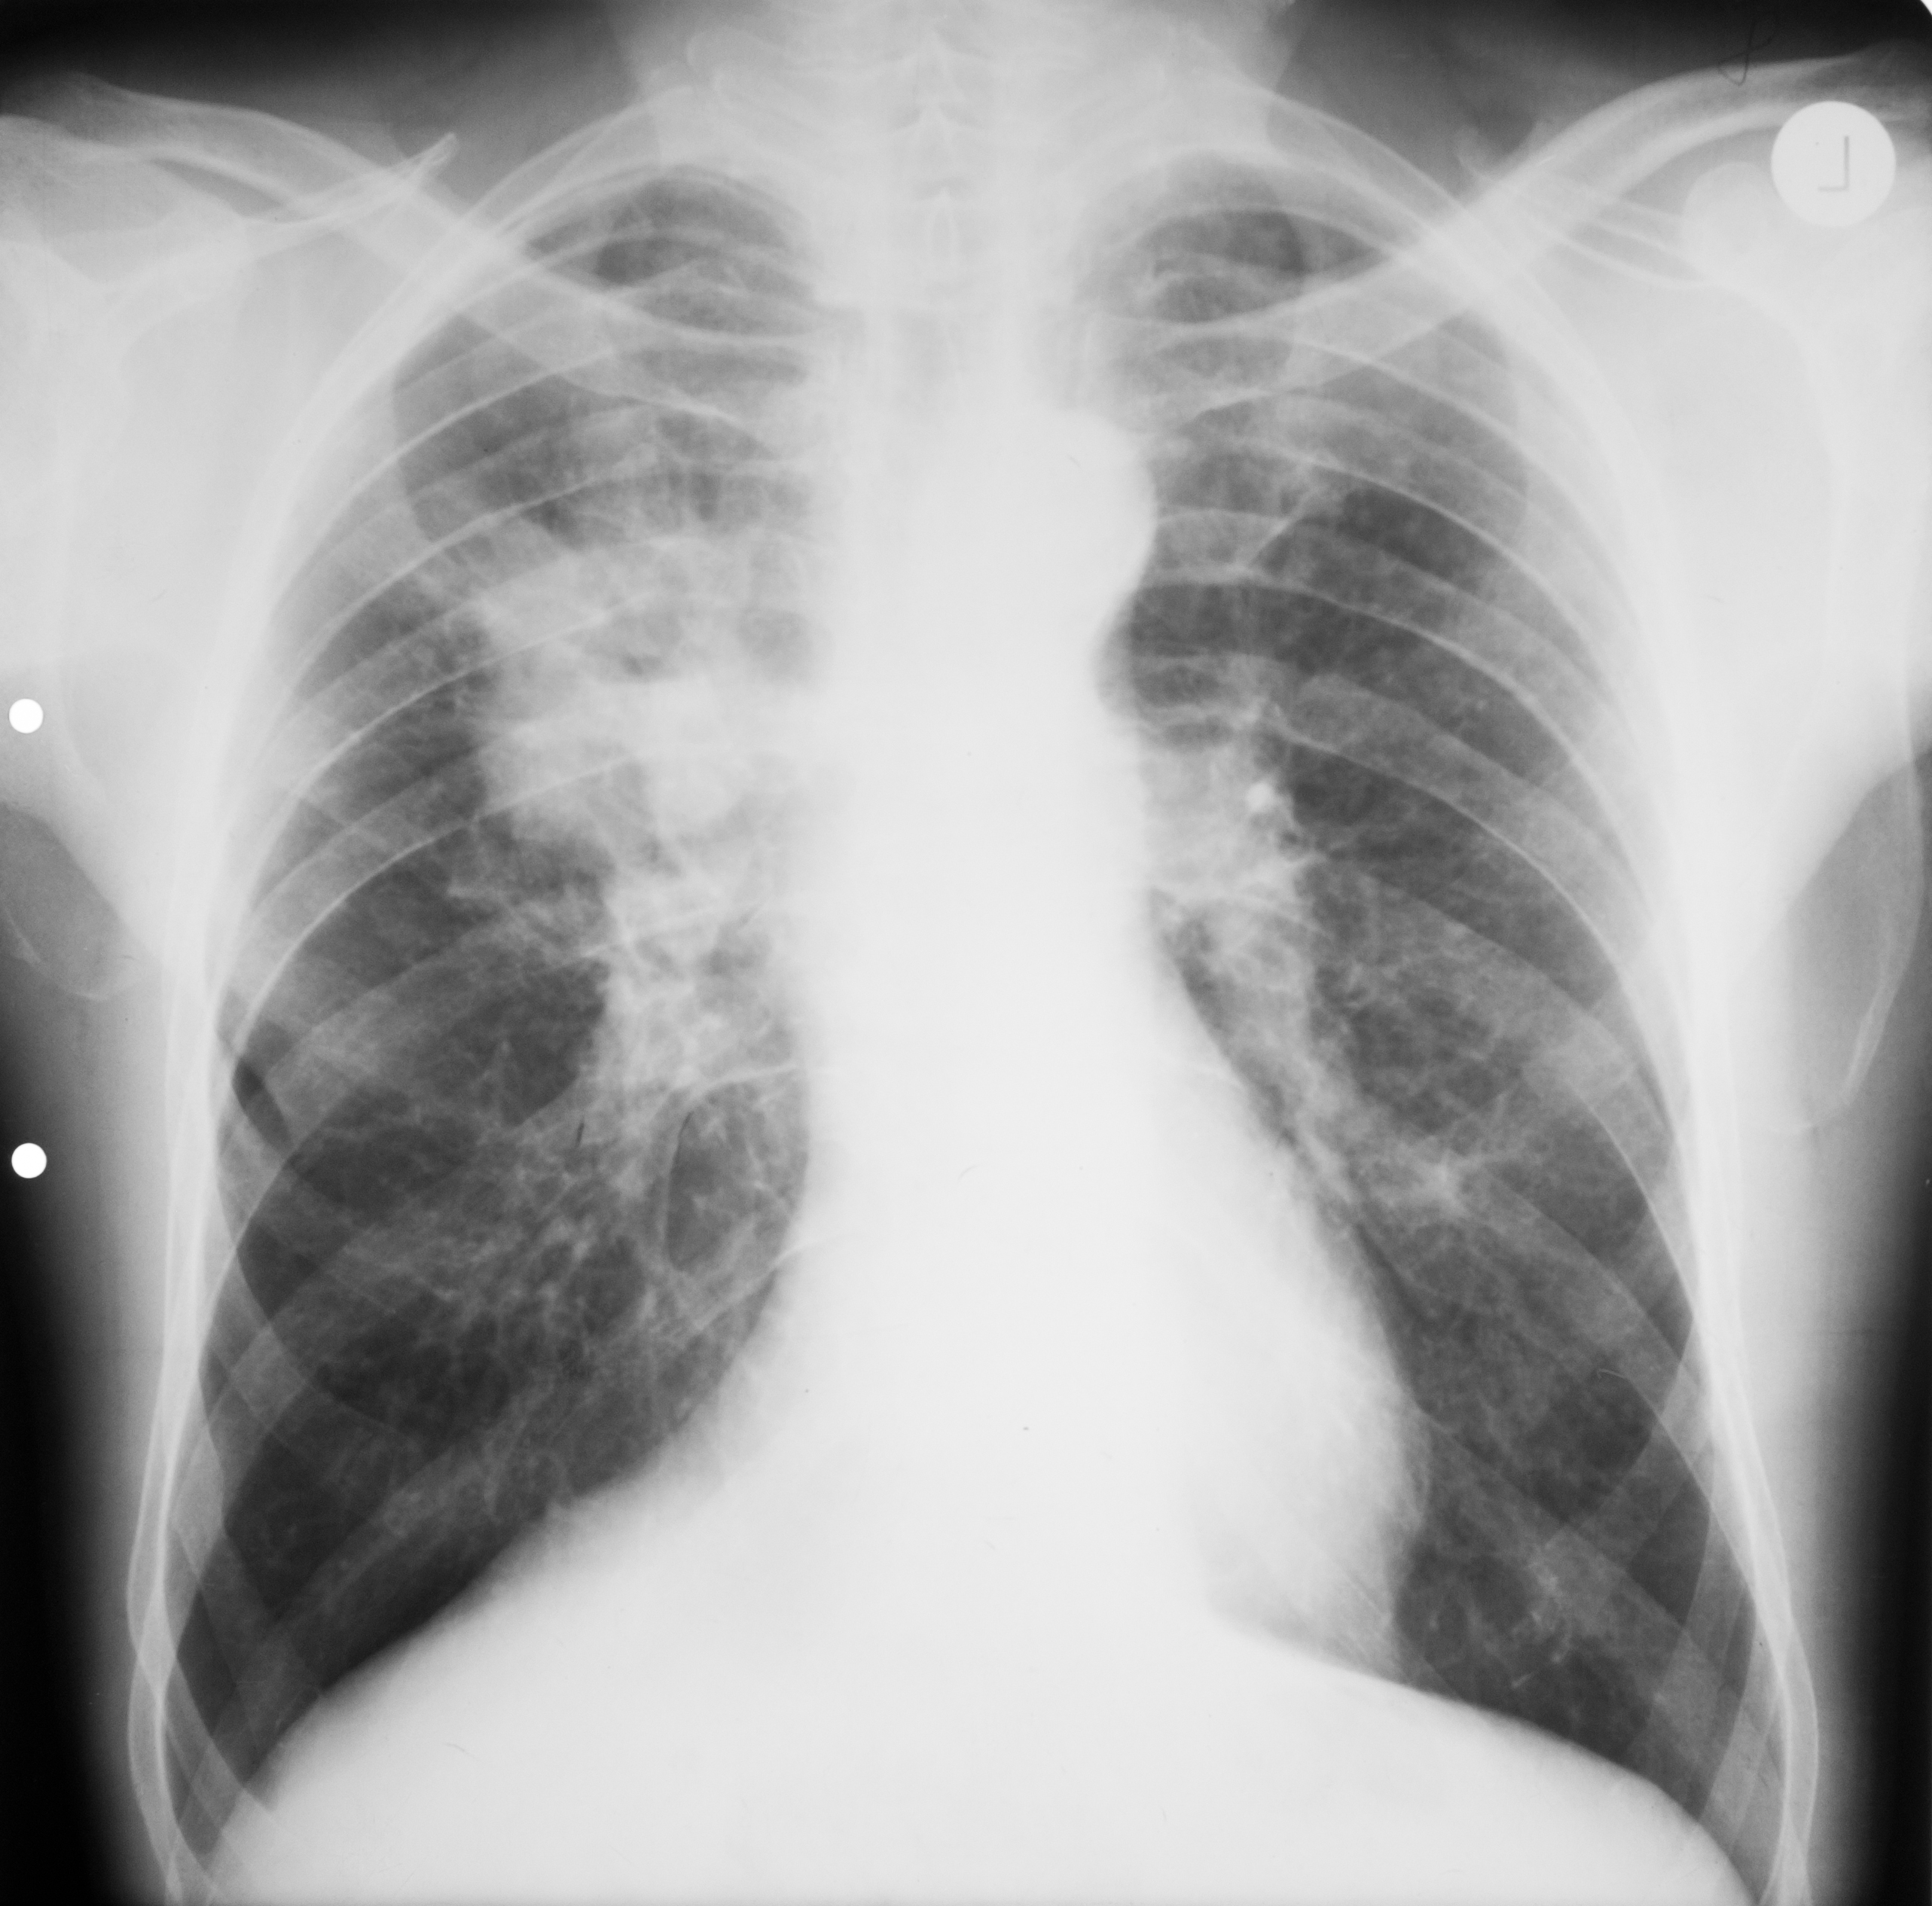

: DETERMINĂRI SECUNDARE-METASTAZE

Opacități macronodulare și nodulare,de dimensiuni variate,omogene,diseminate în ambele câmpuri pulmonare,intensitate medie.De obicei,aceste metastaze apar în cancerul renal sau seminomul